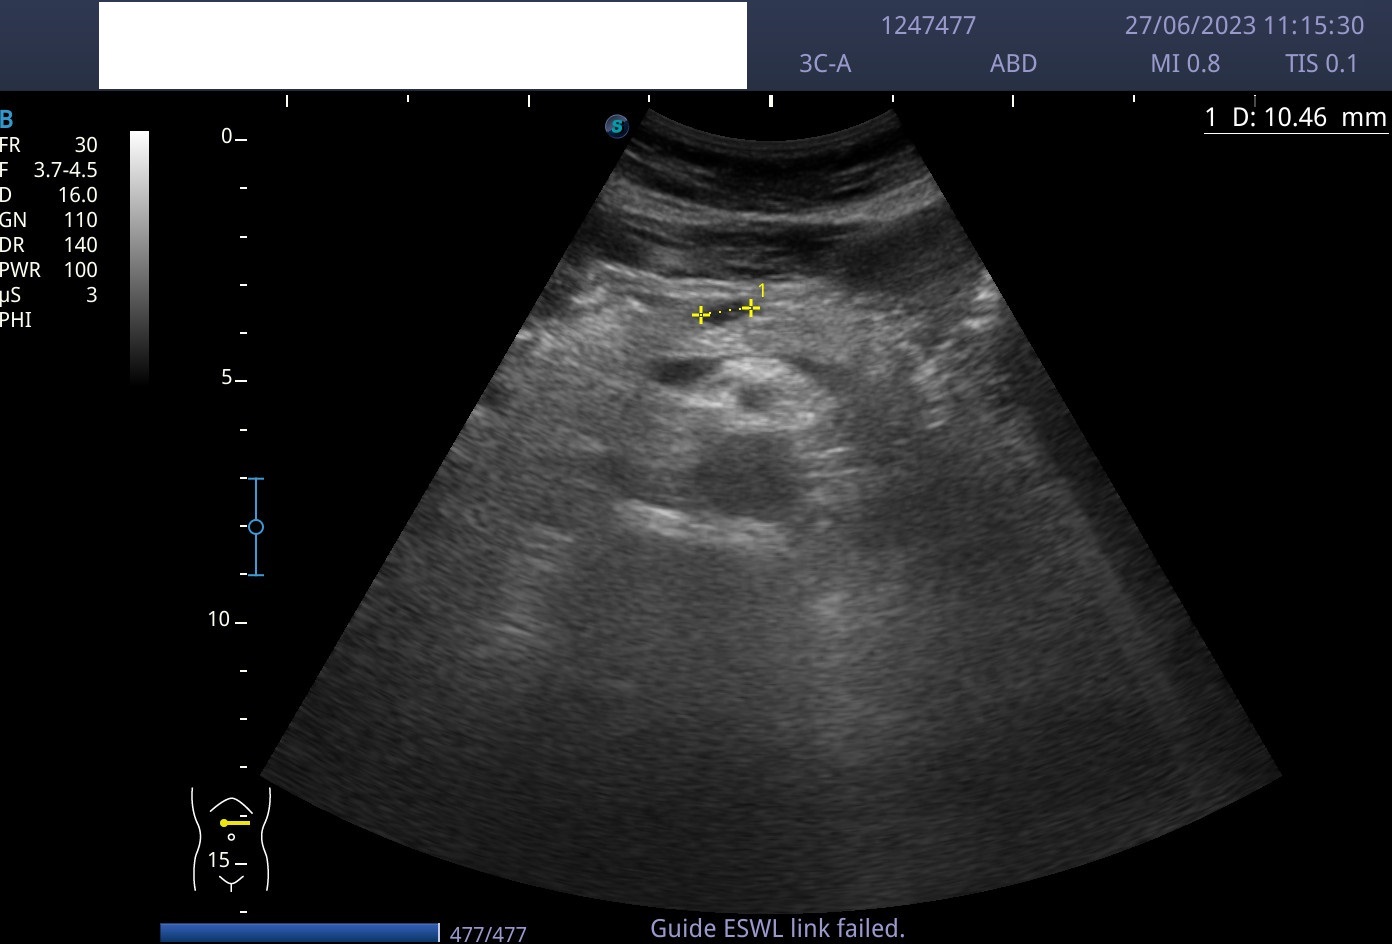

Hallazgos ecográficos

Lesión anecoica bien circunscrita de paredes lisas, con refuerzo posterior, de 1 cm de longitud, localizada en cuerpo pancreático, sin captación Doppler.

Observación. Control ecográfico reglado tri-semestral.

Sin cambios.